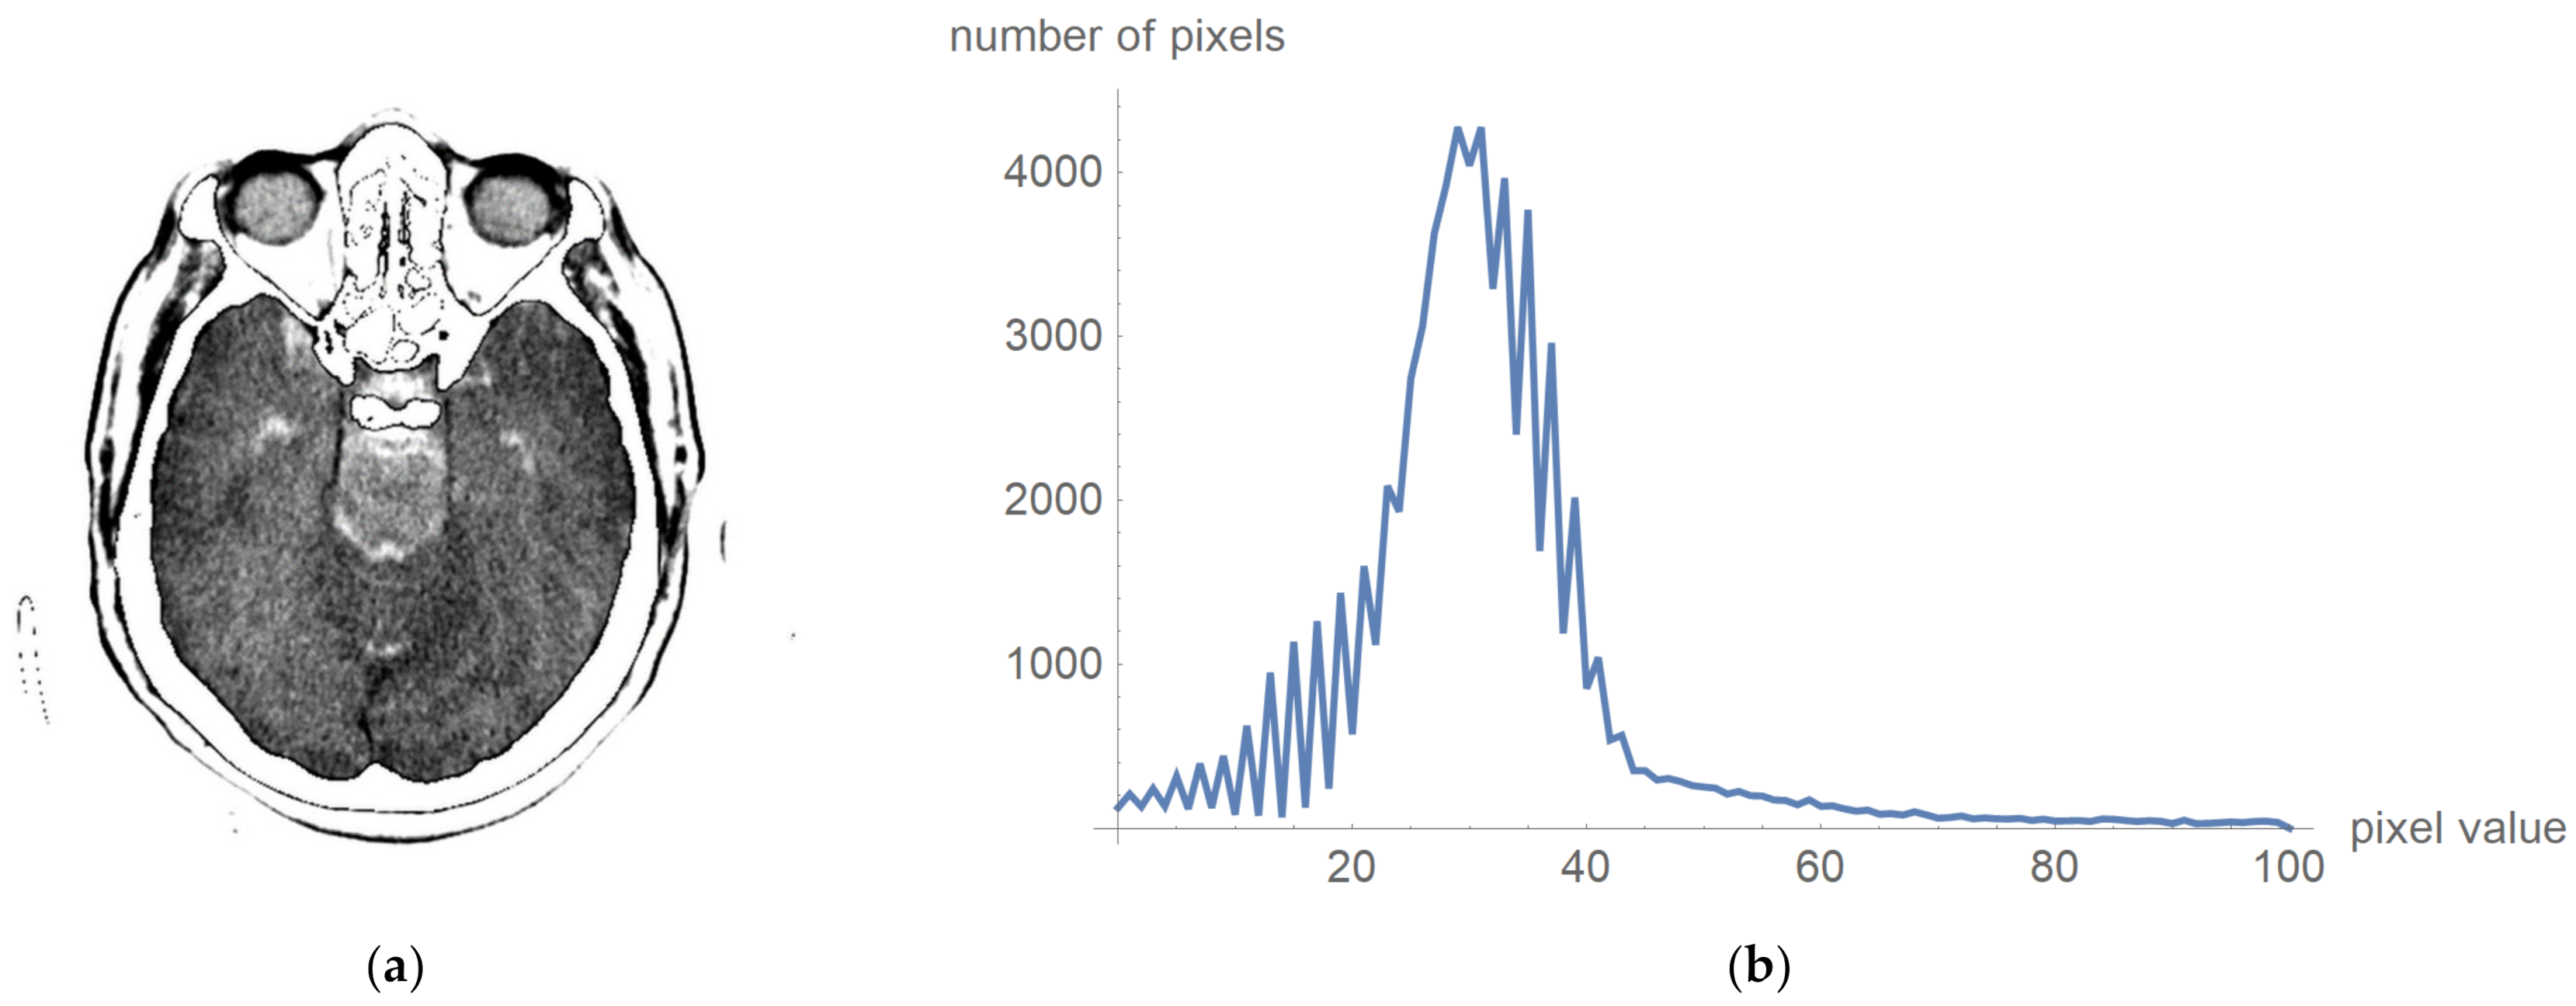

2.2. Smart Visualization Method (SVMI)

3.1. Technological Description